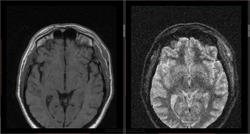

- https://radiomed.ru/sites/default/files/styles/case_slider_image/public/user/16807/3_22.jpg?itok=i_xXDvqx

- https://radiomed.ru/sites/default/files/styles/case_slider_image/public/user/16807/4_12.jpg?itok=JIJx1gcZ